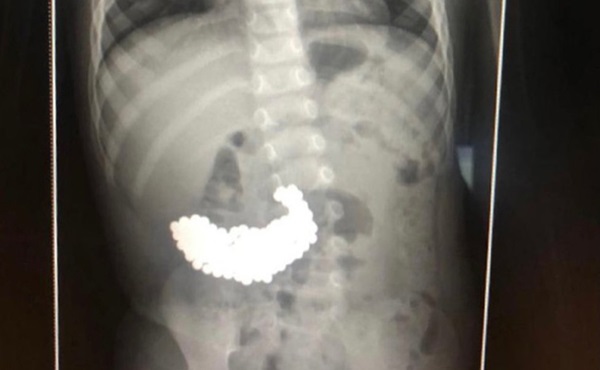

Chỉ mới 2 tháng trước, hồi tháng 2, dịch vụ báo chí của sở y tế Moscow đưa tin, các bác sĩ phẫu thuật tại Bệnh viện Nhi đồng 9 mang tên Speransky ở Moscow đã lấy ra 117 quả bóng từ tính trong dạ dày của một đứa trẻ 1 tuổi.

Cậu bé chơi cùng chị gái, đến khi mẹ bọn trẻ dọn dẹp đồ chơi, phát hiện thiếu bóng từ tính và lập tức đưa cả 2 con đến bệnh viện kiểm tra. Bé gái lớn hơn không có vấn đề gì nhưng bác sĩ phát hiện nhiều bóng từ tính trong bụng bé trai 1 tuổi. Cậu bé được khẩn trương đưa vào phòng mổ.